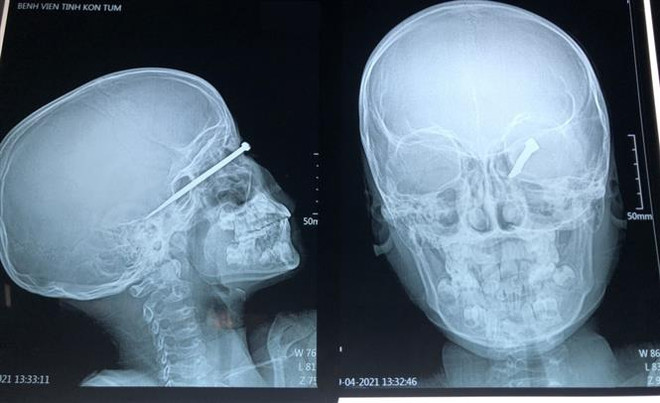

Đi bắt chuột rạng sáng, bé trai 8 tuổi bị bạn bắn trúng mắt trái ảnh 1Hình ảnh cận lâm sàn của bệnh nhân A.T bị dị vật đâm xuyên nhãn cầu vào nền sọ. (Ảnh: TTXVN phát)

Qua thăm khám và chụp chiếu, các bác sỹ nhận định bệnh nhân A.T bị một dị vật là kim khí tự chế cắm xuyên nhãn cầu và đi sâu tới nền sọ.

Các bác sỹ đã hội chẩn và quyết định thực hiện phẫu thuật gấp. Các y, bác sỹ tại Khoa Ngoại chấn thương - Bệnh viện Đa khoa tỉnh Kon Tum đã lấy thành công dị vật là 1 thanh kim loại được mài nhọn có kích thước 0,5x8cm, tương đương một chiếc đinh thường dùng trong xây dựng.